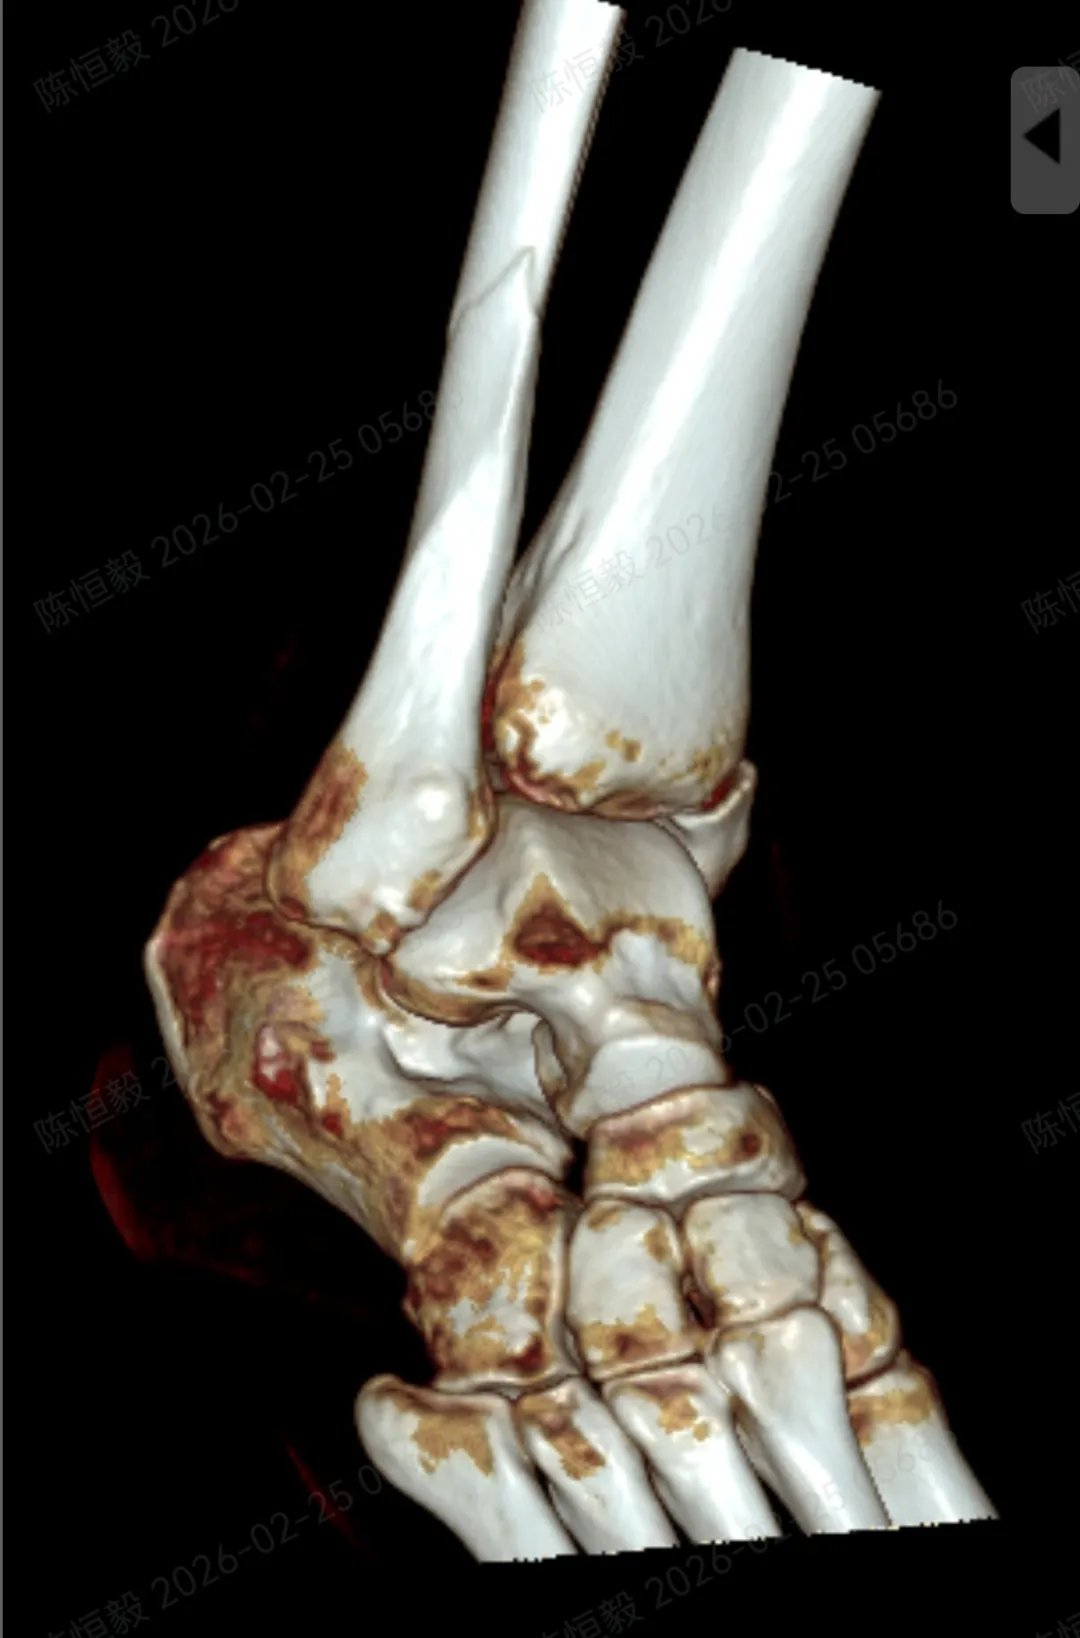

王女士在西安旅游时不慎崴伤脚踝,当即出现疼痛、活动受限的情况,在当地医院就诊后,被诊断为踝关节骨折,建议接受手术治疗。

针对王女士的踝关节骨折情况,由副主任医师陈涛主刀,足踝外科团队为其实施了关节镜辅助下机器人导航微创闭合复位内固定术

对于踝关节骨折的诊疗而言,关节面复位的精准度直接关系到远期恢复效果,若复位存在偏差,可能增加创伤性关节炎、慢性疼痛、关节功能障碍等问题的发生概率。

本次诊疗中,在关节镜直视下确保骨折部位实现解剖复位,同时对检查中发现的合并软骨损伤进行了同步处理,为关节的后续恢复提供了保障。